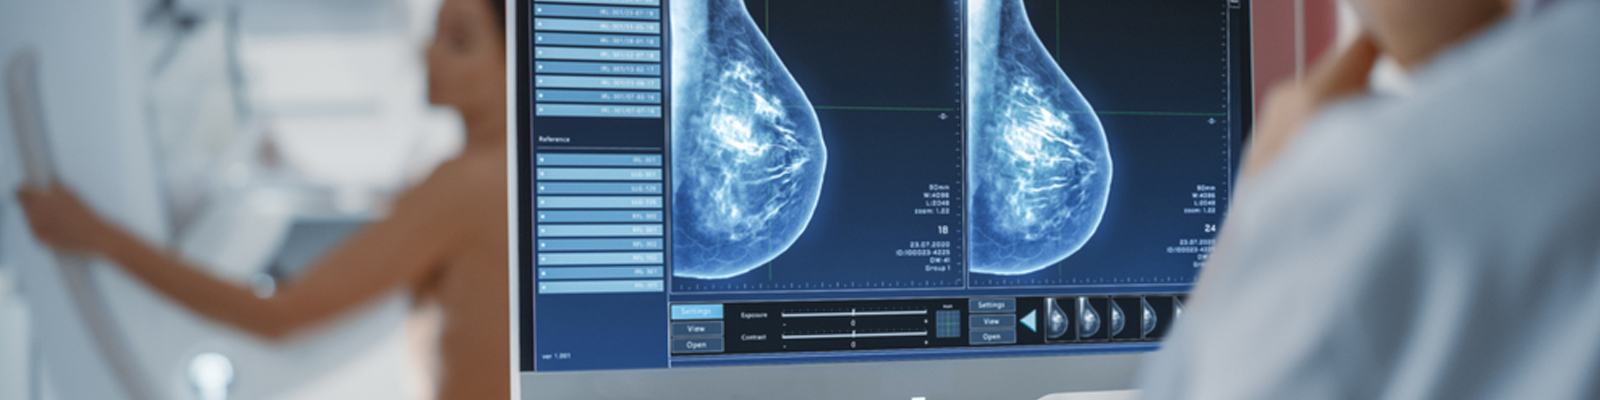

Here’s a breakdown of the top preventive health screenings for women, categorized by age group:

We offer affordable and comprehensive women’s health checkups in West Tambaram, which include: